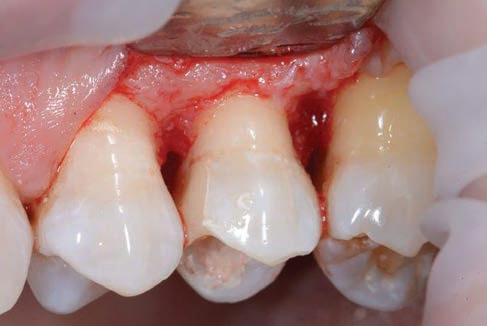

Figure 5: Clinical crown lengthening with a minimally invasive technique without mesial and distal discharges. Note the proximity of the reconstruction in glass hybrid material to the mesial bone ridge.

The third step of the treatment consisted of the crown lengthening, necessary to expose an adequate part of the root to obtain, after healing, the correct adhesion of the composite for the pre-prosthetic restoration and the successive prosthetic rehabilitation.

After the surgical flap elevation of the tissue and the bone remodeling, the flap was repositioned apically and sutured with a vertical mattress suture anchored in the periosteum (Figs. 5-6). The suture was removed after 7 days (Fig. 7).